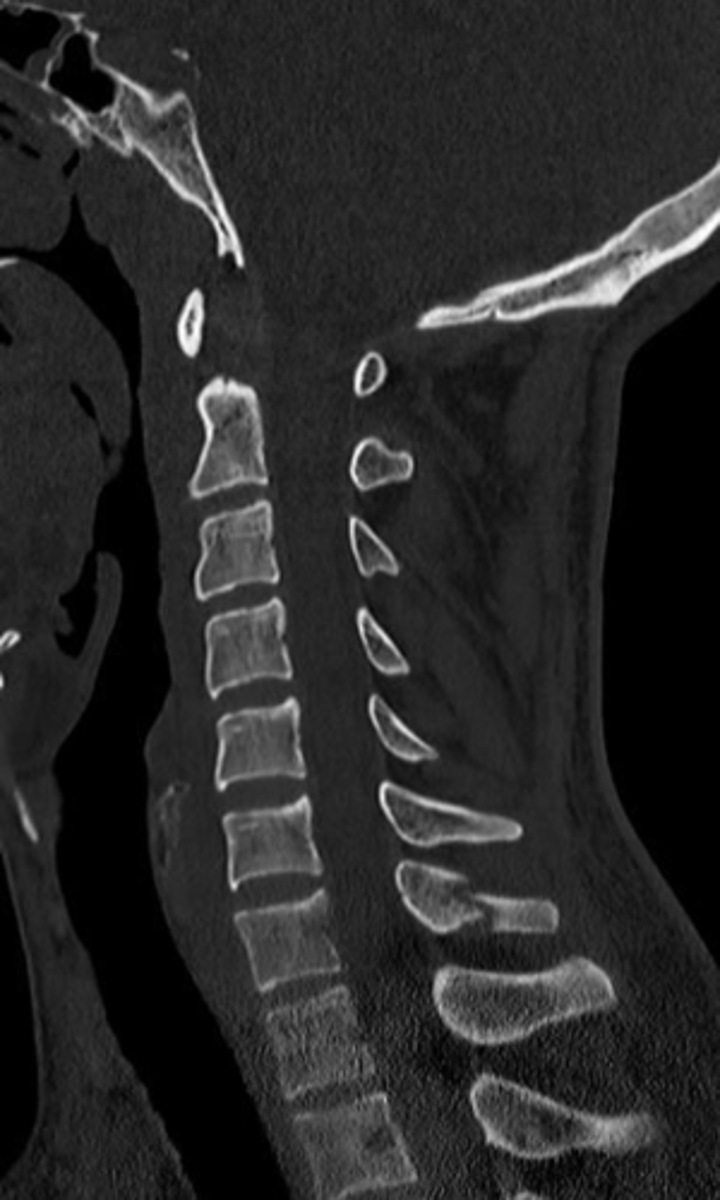

hangman's fracture is a fracture of the

bilateral pars interarticularis of C2

hangman's fracture is traumatic _____ of the atlas/axis

spondylolisthesis of the axis (C2)

what are the most common causes of a hangman's fracture

MVA, diving injuries, sports injuries, face first fall from standing position

Jefferson's fracture is a ___ fracture of the atlas/axis caused by axial loading of the cervical spine

burst fracture of the atlas (C1)

are jefferson's fractures usually accompanied by c-spine injuries?

yes, 1/3 have c2 fracture